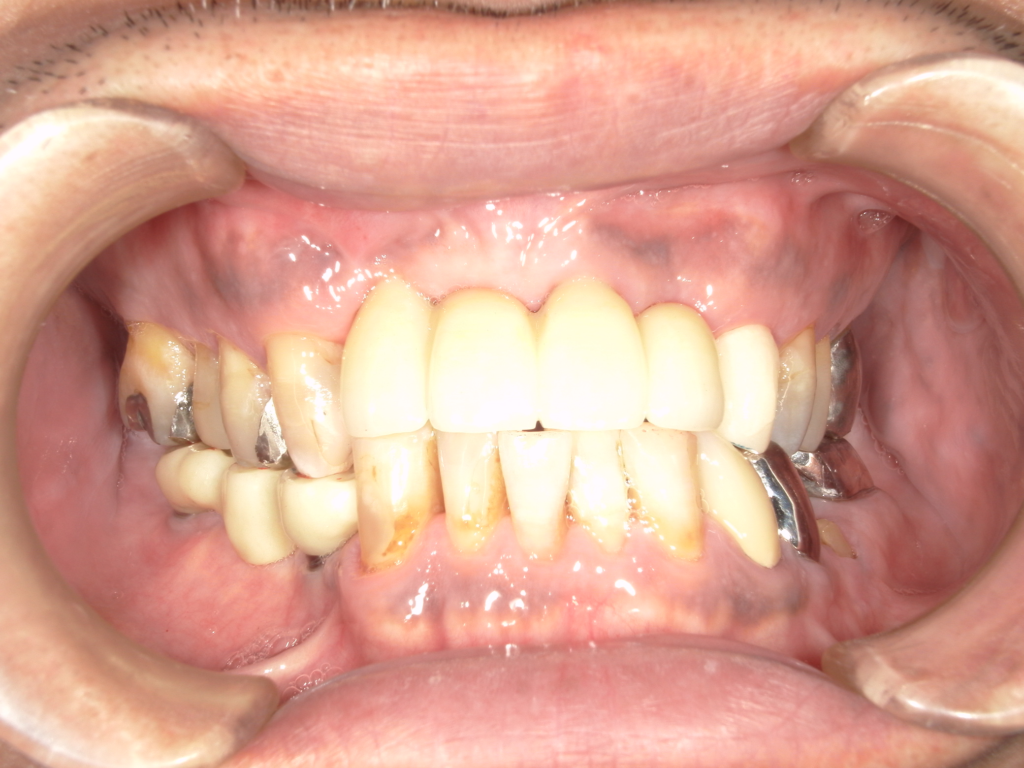

Y様インプラント実例 #44

左の上下の奥歯をインプラントで治療しています。

左下の奥歯は歯を抜くのと同時にインプラントの埋め込みを行っています。

被せものは上下、セラミックスで作っています。

治療前

治療後